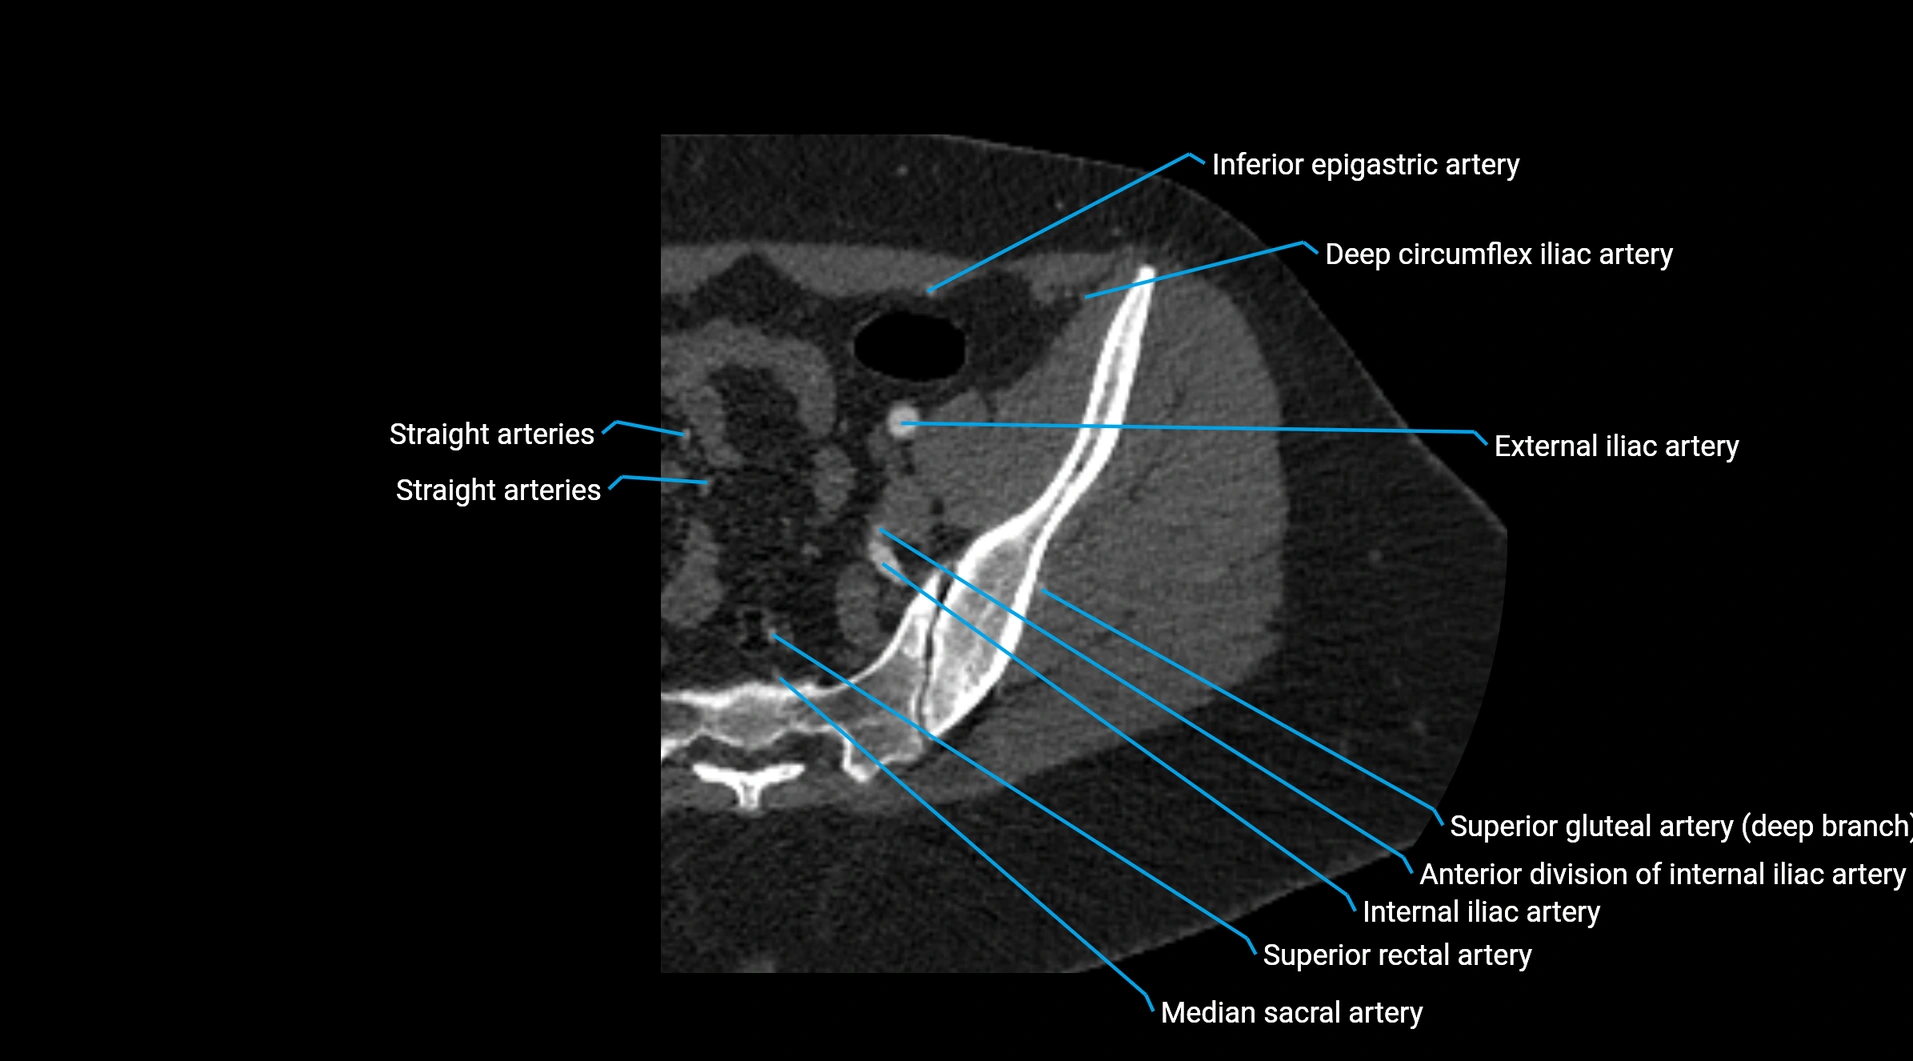

Contrast-enhanced CT (CTA):

• Gold standard for abdominal aortic imaging

• Provides excellent detail of lumen, wall, aneurysm, thrombus, and branch vessels

• Multiplanar and 3D reconstructions help in aneurysm measurement, stent graft planning, and dissection evaluation